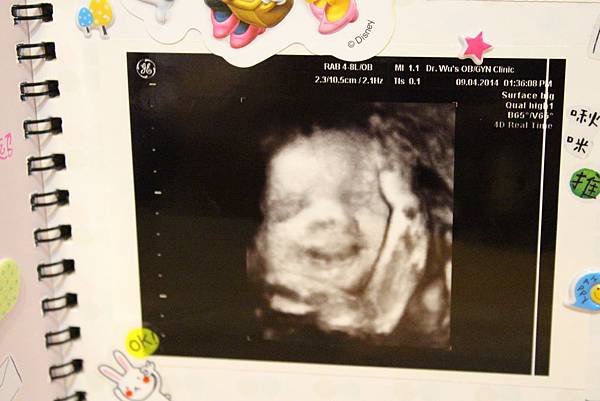

【孕期】小Abby笑得好開心